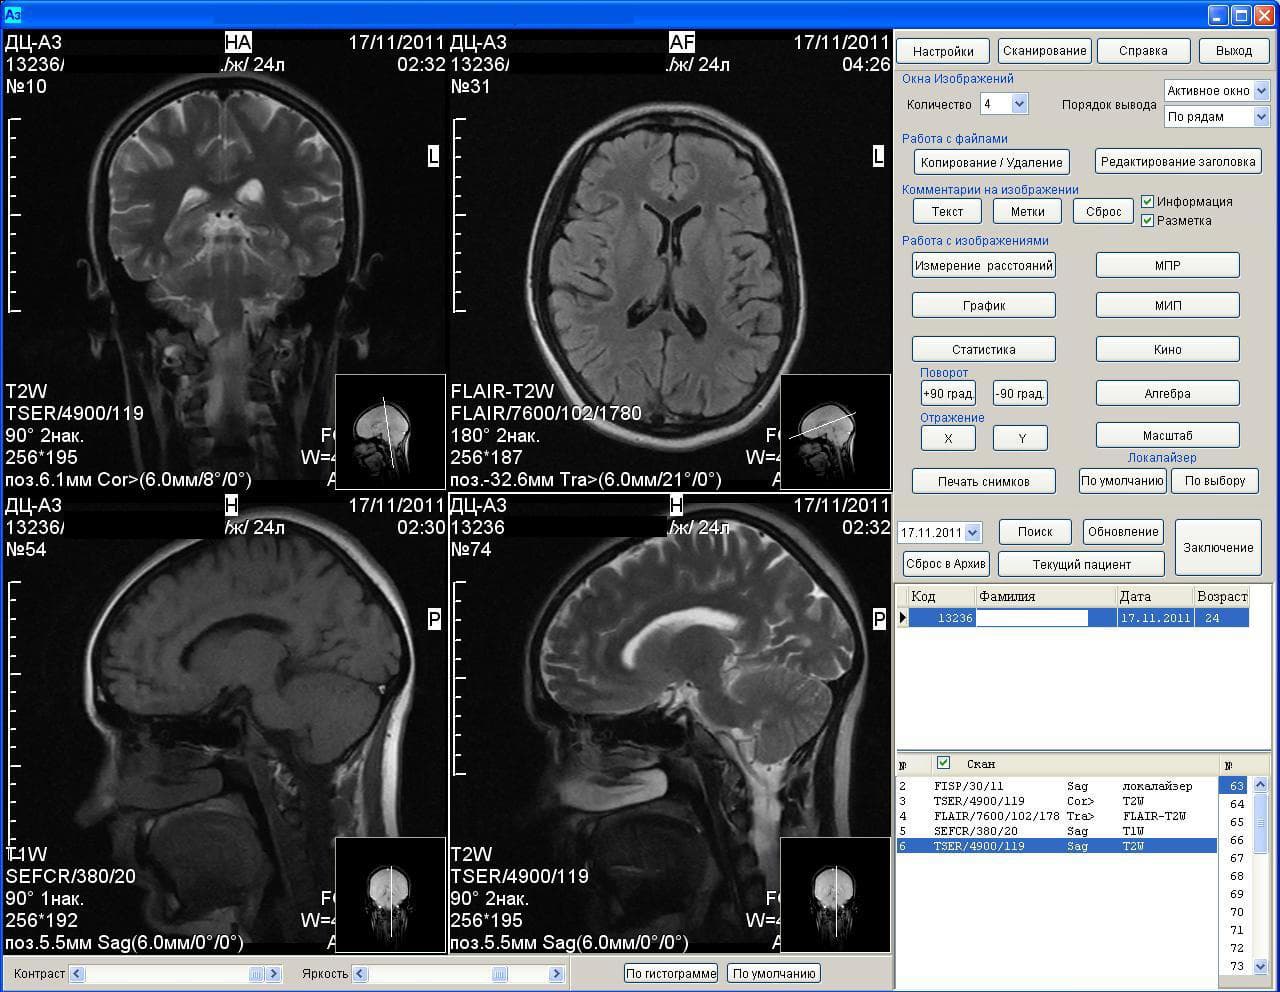

Результаты аппарата МРТ Аз-300

Отмечается, что ученые восстановили функциональные сети головного мозга здоровых людей и пациентов с депрессией. Методика, получившая название «консенсусный подход», выявила различия в результатах функциональной МРТ у двух групп людей.

Разработка российских ученых позволяет с высоким уровнем точности определить депрессию. В ближайшее время специалисты БФУ планируют создать систему автоматического распознавания депрессии с помощью МРТ.